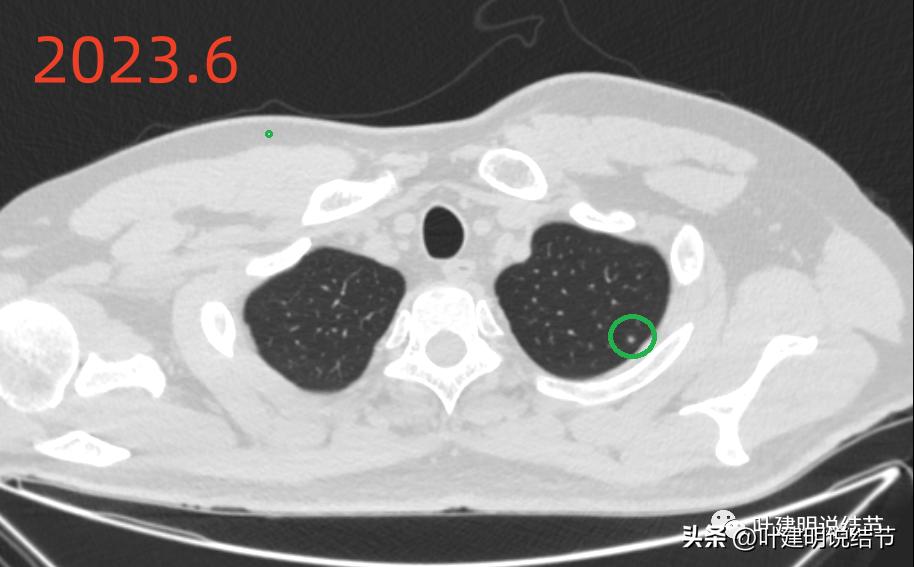

再来看2023年6月的影像情况:

左上病灶C仍在,而且密度与2019年时比,感觉略高,大小没什么变化,基本上是良性的,纤维增生结节可能性大。

左下病灶A仍在,感觉较前略有收缩,而且它旁边原来在2019年时有的磨玻璃结节已经完全吸收。考虑慢性炎可能性更大些。

左下病灶B持续存在,密度略有增高的样子,轮廓清楚,有微小血管征,仍要考虑肿瘤范畴的,以原位癌可能性稍大,大小无明显进展。

绿色圈起来的左上叶微小结节一直有,密度高,轮廓略糊,考虑是良性纤维增生结节;黄色圈起来的右侧的小片状磨玻璃影,非圆形或类圆形,且对比无进展,考虑是少许纤维增生。左下主病灶持续存在,轮廓较为清楚,但实性成分不明显,考虑不典型增生或原位癌可能性较大,目前风险不算高,个人以为仍可随访;左下次病灶密度显高,边缘略糊,不太像恶性。原来又炎症过,对比此前此处刚好是炎症较为明显的位置,所以比较符合慢性炎点,目前风险低,能随访。意见供参考!